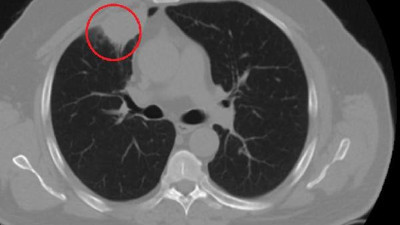

Dünya tıp literatüründe bir ilk. Korona akciğer kanserini taklit etti Kahramanmaraş'ta akciğer kanseri teşhisi konulan N.T.'nin (52) ameliyat öncesi korona virüs testi pozitif çıktı. 14 günlük korona tedavisinin ardından yeniden çekilen tomografisinde akciğeri temiz çıktı. Sütçü İmam Üniversitesi Sağlık Uygulama ve Araştırma Hastanesi Göğüs Cerrahi Ana Bilim Dalı Öğretim Üyesi Dr. Fatoş Kozanlı, koronavirüsün akciğer kanserini taklit ettiğini ve bunun dünya tıp literatüründe bir ilk olduğunu söyledi.